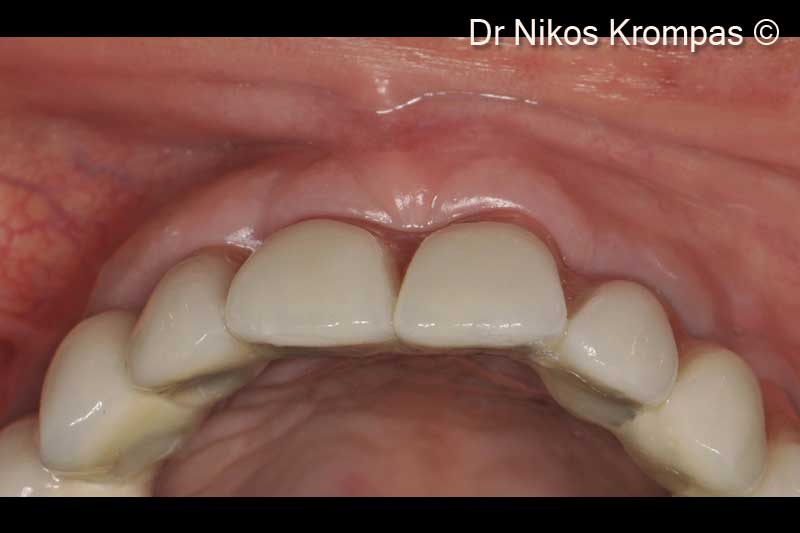

13. Semi-occlusal view of the final bridge. Note the excellent soft tissue contours